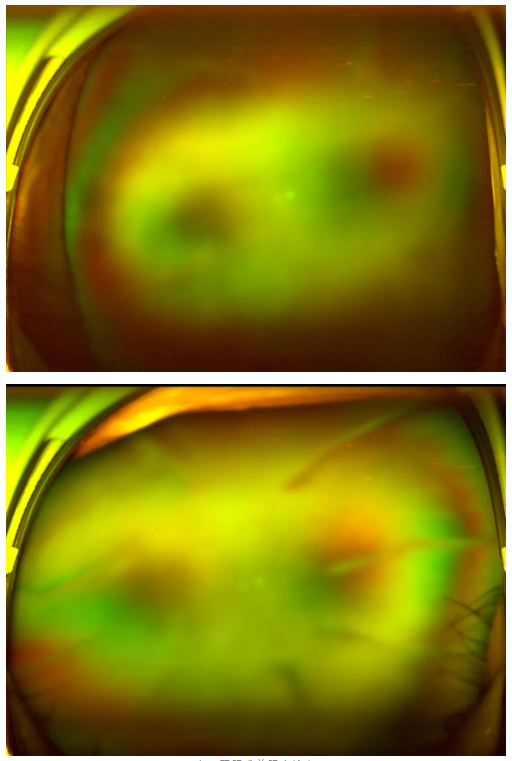

老王雙眼術(shù)前眼底檢查

作為深耕眼科領(lǐng)域20余年的專家,王曉波主任擅長復(fù)雜糖尿病視網(wǎng)膜病變的診斷與治療,臨床經(jīng)驗極為豐富。接診后,他為老王進行了全面細(xì)致的檢查,發(fā)現(xiàn)老王雙眼視力確實極差——右眼僅剩眼前指數(shù),左眼僅剩手動指數(shù),但眼底病變情況并未到無法挽救的程度;此外,他還合并有雙眼老年核性白內(nèi)障,這也是導(dǎo)致他進一步加劇視力下降的原因之一。

王曉波主任告知老王:術(shù)后復(fù)查眼底顯示,其糖尿病視網(wǎng)膜病變并不嚴(yán)重,因此視力得以得到明顯改善與提升。當(dāng)初堅持治療、不輕言放棄,是非常正確的選擇!